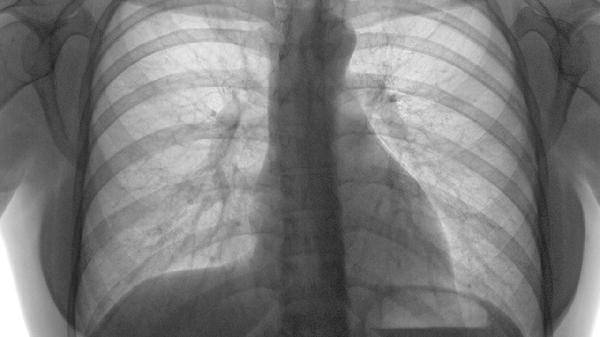

单纯线性骨折稳定性较高,打喷嚏产生的胸腔压力变化通常不会造成二次损伤。粉碎性骨折或伴有移位的骨折需外固定保护,此时剧烈动作可能影响愈合。

急性期(2-3周)骨痂未形成时需避免剧烈咳嗽或喷嚏,可通过按压患侧胸部减轻震动。纤维骨痂期(3-6周)后打喷嚏的冲击力多能被新生骨组织缓冲。